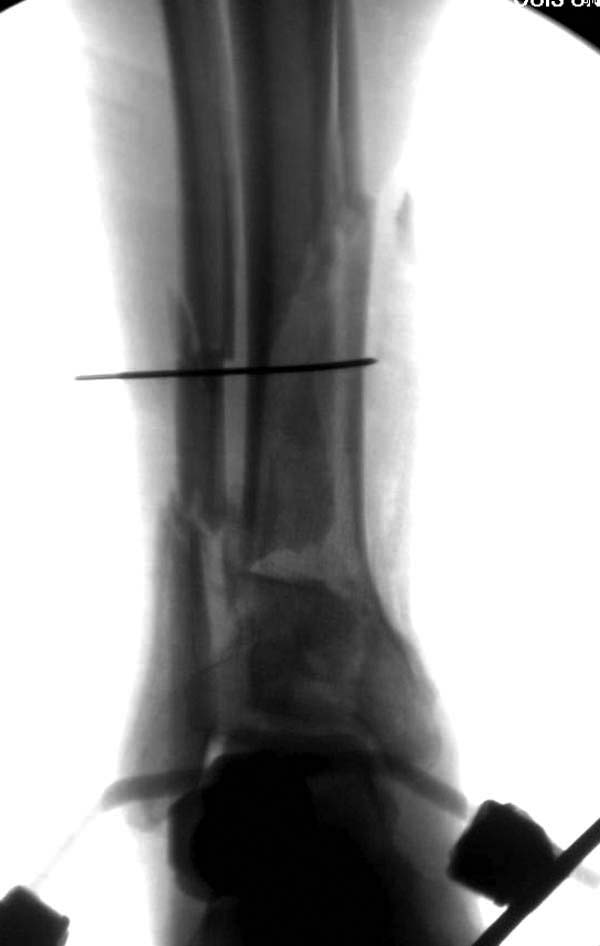

До лечения, в процессе, через 8 мес.

Современную тактику лечения переломов пилона описали коллеги, а мне остается подтвердить клинически. В многоэтапном лечении главное - это предупреждение сокращения мягких тканей, от которого зависит судьба конечности. Дистракция любым наружным фиксатором, и по готовности мягких тканей - премежуточная или окончательная фиксация.

Вначале нет смысла заказывает КТ, только дистракция организует на свое место свободных фрагментов. По топографии отломком преоперационный план, а готовность мягкой ткани подтвердит появившиеся морщины на поверхности кожи, “Wrinkle Sign”.

Трудно предсказать, что в течение именно двух недель решится готовность к операции. Все зависит от энергии травмы, иногда образование морщин ждали более чем две недели. Любая интервенция без подготовки кожных покровов - это риск осложнений!

Через три дня повторная I&D, где через рану манипулировали дистальным фрагментом с установкой пары межфрагментарных шурупов. На рану вакуум и следующая обработка закончилась закрытием раны. Отек держался немного дольше, чем обычно.

После спадения отека вариантов фиксации много, включая мининвазивную технику, но данный случай закончили установкой простого аппарата Илизарова.